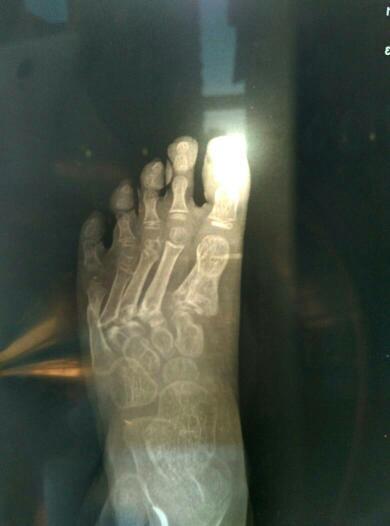

四岁小孩因为车祸导致右脚跖骨1-5粉碎性骨折,目前已经七个月,小拇指跟大拇指差不多长好了2-4三个 四岁小孩因为车祸导致右脚跖骨1-5粉碎性骨折,目前已经七个月,小拇指跟大拇指差不多长好了2_4三个脚趾恢复不乐观,靠近骨骺这个地方明显往做歪,骨头也没有对齐,医生说骨骺伤的厉害怕骨头不长, 点击展开 匿名用户 2016-03-28 18:08 满意回答 建议外敷专门针对骨折康复的膏药,可以接骨续筋促进骨头愈合 匿名用户 2016-03-29 09:03 宝宝知道提示您:回答为网友贡献,仅供参考。 相关问题 右脚234跖骨粉碎性骨折,钢板固定手术2月,现 三岁宝宝被压面机压断大拇指小拇指!以后能接好吗? 脚的小拇指比和大拇指一样长,这是为何?